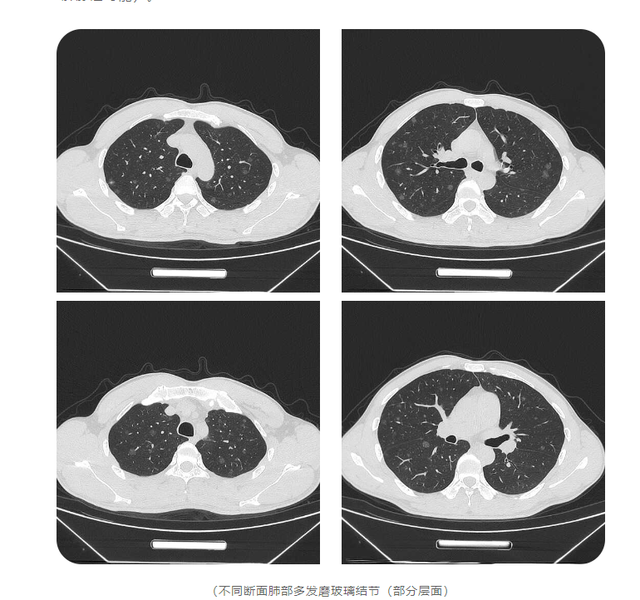

右肺下叶病变,考虑为炎性病变可能;右肺中叶外侧段结节灶,不除外肺内